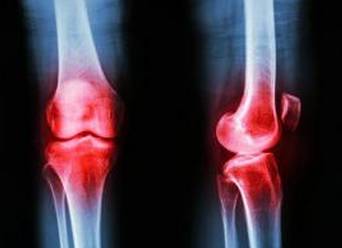

如果这些您都说“是”,那么就要当心是骨性关节炎了。得了这个病,最常见的就是膝关节疼。

骨性关节炎(osteoarthritis,OA)或称退变性关节炎、老年性关节炎、增生性关节炎。该病可能是这世界上最古老且最具慢性特征的疾病。在史前人类和恐龙的化石遗迹中,都能发现骨关节炎的痕迹。有关骨关节炎的记录可以追溯到古代,通过对埃及木乃伊的研究可以清楚地看到骨关节炎的存在。

骨性关节炎实际上并非炎症,主要为退行性变,属关节提前老化,特别是关节软骨的老化,属中医学骨痹、膝痹范畴,发生率随年龄的增高而增多,症状多出现在40岁以后,可以说是一个老年人的关节病,随着年龄的增长,一个或多个关节罹患骨关节炎的人群比例越来越高。